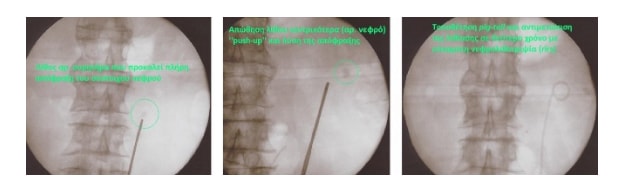

Η αντιμετώπιση της αποφρακτικής ουροπάθειας περιλαμβάνει την άμεση παροχέτευση των ούρων, ιδίως στην περίπτωση της επιπλοκής με λοίμωξη ή έκπτωσης της νεφρικής λειτουργίας.

Η παροχέτευση των ούρων μπορεί να γίνει, ανάλογα με το επίπεδο της απόφραξης, είτε με καθετηριασμό της ουροδόχου κύστης, του ουρητήρα ή και με νεφροστομία.